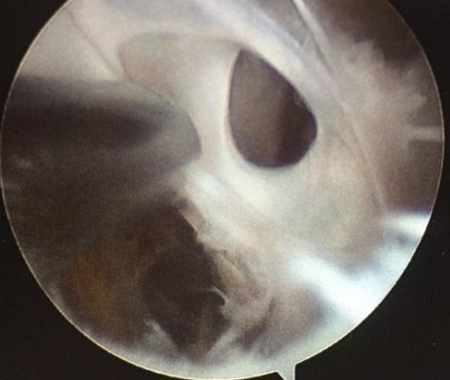

Arthroscopic resection facilitates management of the cyst (by arthroscopic decompression) and the associated intra-articular disorder. Surgery involves enlarging the interval between the semimembranosus and medial gastrocnemius, allowing the cyst contents to drain into the joint. Arthroscopic resection is effective, and is associated with reduced morbidity and recurrence compared with excision.[24][25][26][Figure caption and citation for the preceding image starts]: Arthroscopic resection of a popliteal cystFrom the collection of Dr John Kelly IV; used with permission [Citation ends].

[Figure caption and citation for the preceding image starts]: Arthroscopic resection of a popliteal cystFrom the collection of Dr John D. Kelly IV; used with permission [Citation ends].